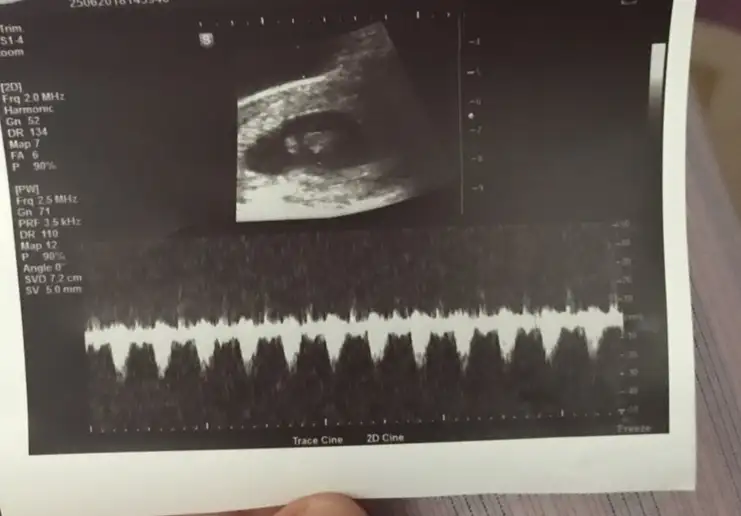

Ultrason da yazıyor 119 Muş benim baktım :)BEN SORDUM ..SORMADAN SÖYLEMİYORLAR DAKİKADA KAÇ ATTIĞINI CANIM

Nerde yaziyo canim bende bakayimUltrason da yazıyor 119 Muş benim baktım :)

Ikimizin ayni acaba DR yazan yer mi benimde DR 163Benim de farklı acaba hangisi

Bana da o gibi geldi ama o da altta üstte iki tane farklı yazıyoIkimizin ayni acaba DR yazan yer mi benimde DR 163